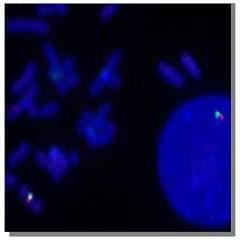

Próbki sond FISH:

Sonda do malowania ludzkiego chromosomu 1 (zielony) |

Ludzki chromosom e 1 sondy subtelomerowe |